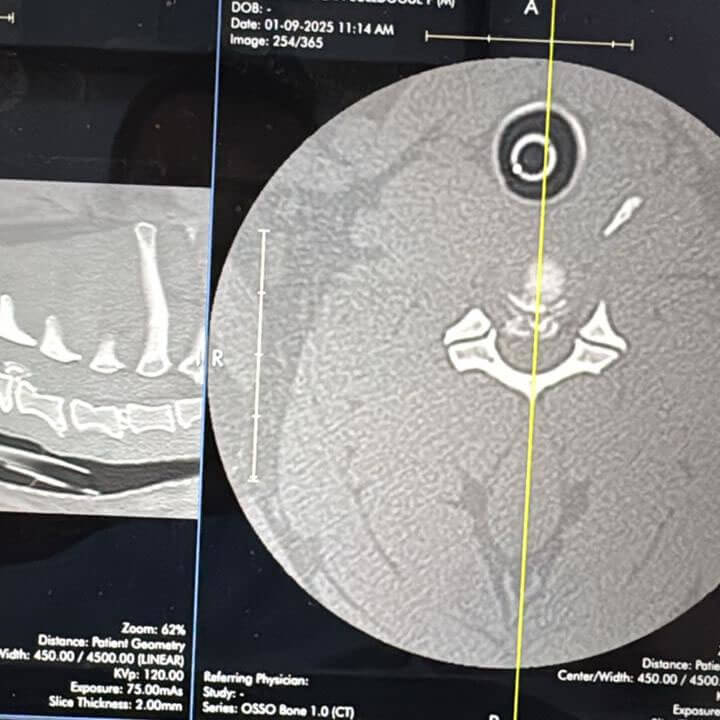

Hérnia de

Disco

Doença grave que causa paralisia e muita dor. Precisa de abordagem urgente